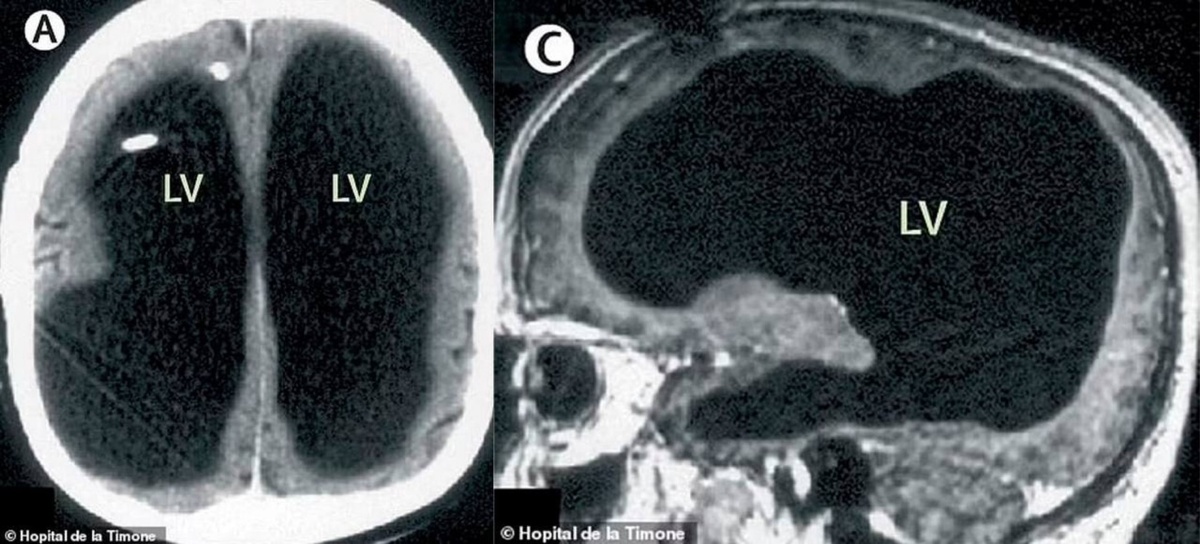

Это не гипотетический эксперимент. В 2007 году весь медицинский мир облетела статья The Lancet. 44-летний мужчина пришел к врачу с жалобой на слабость в ноге. Когда ему сделали МРТ, чтобы заглянуть внутрь, врачи чуть не выронили кофе. 90% (по некоторым данным до 98%) его черепной коробки занимала жидкость. Нейроны? Серое вещество? Их почти не было. Гидроцефалия сожрала их за десятилетия. Но этот человек был нормальным. Женат, работает в госслужбе, воспитывает двоих детей. Коэффициент интеллекта — 75 (не гений, но и не овощ). Разбор для гиков:

The Lancet. 44-летний мужчина пришел к врачу с жалобой на слабость в ноге. Когда ему сделали МРТ, чтобы заглянуть внутрь, врачи чуть не выронили кофе. 90% (по некоторым данным до 98%) его черепной коробки занимала жидкость. Нейроны? Серое вещество? Их почти не было. Гидроцефалия сожрала их за десятилетия. Но этот человек был нормальным. Женат, работает в госслужбе, воспитывает двоих детей. Коэффициент интеллекта — 75 (не гений, но и не овощ).